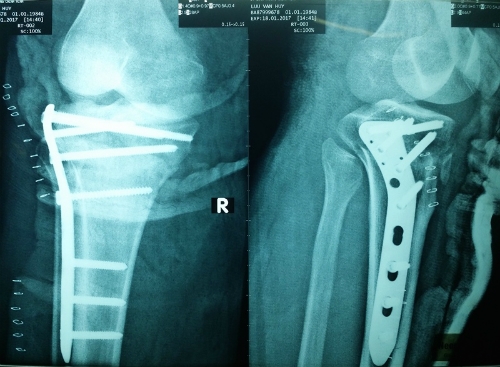

| Kết hợp xương bằng đường mổ ít xâm lấn dưới hỗ trợ của màn tăng sáng. |

Sau 4 giờ kết hợp xương bằng đường mổ ít xâm lấn và ghép nối mạch máu vi phẫu, chân bệnh nhân đã được cứu sống hoàn toàn. Kết quả không những phục hồi giải phẫu xương mà còn phục hồi về lưu thông mạch máu trong một lần mổ duy nhất, hiện tình trạng bệnh nhân dần ổn định.